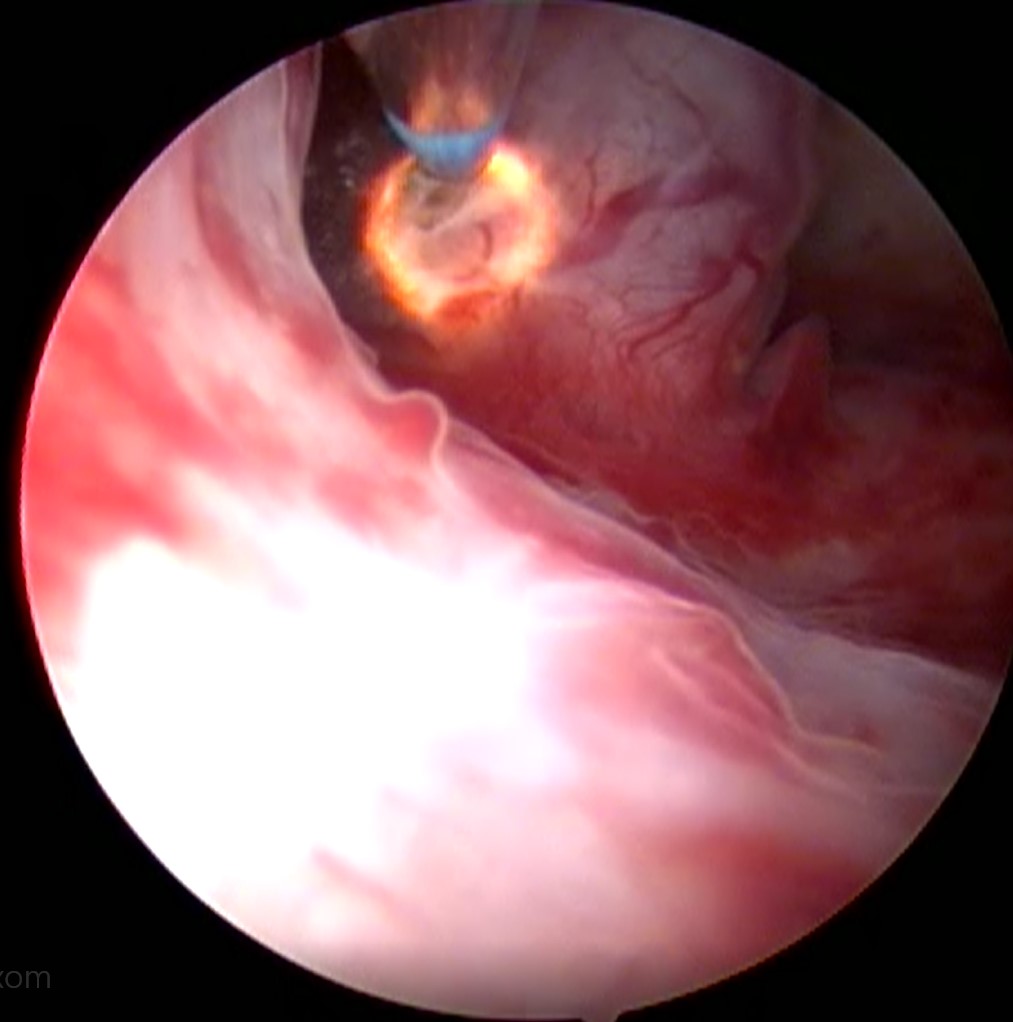

Nejčastější hysteroskopické nálezy

• Nejčastější hysteroskopické nálezy